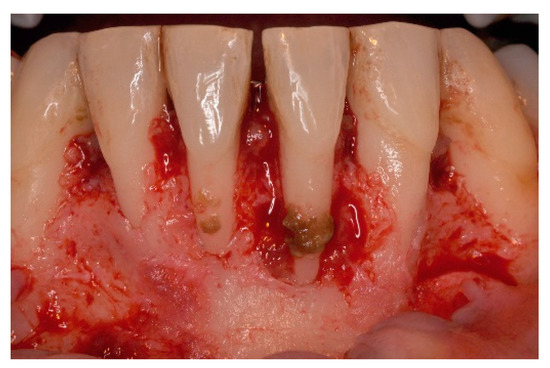

5. Materials and Methods

6. Results